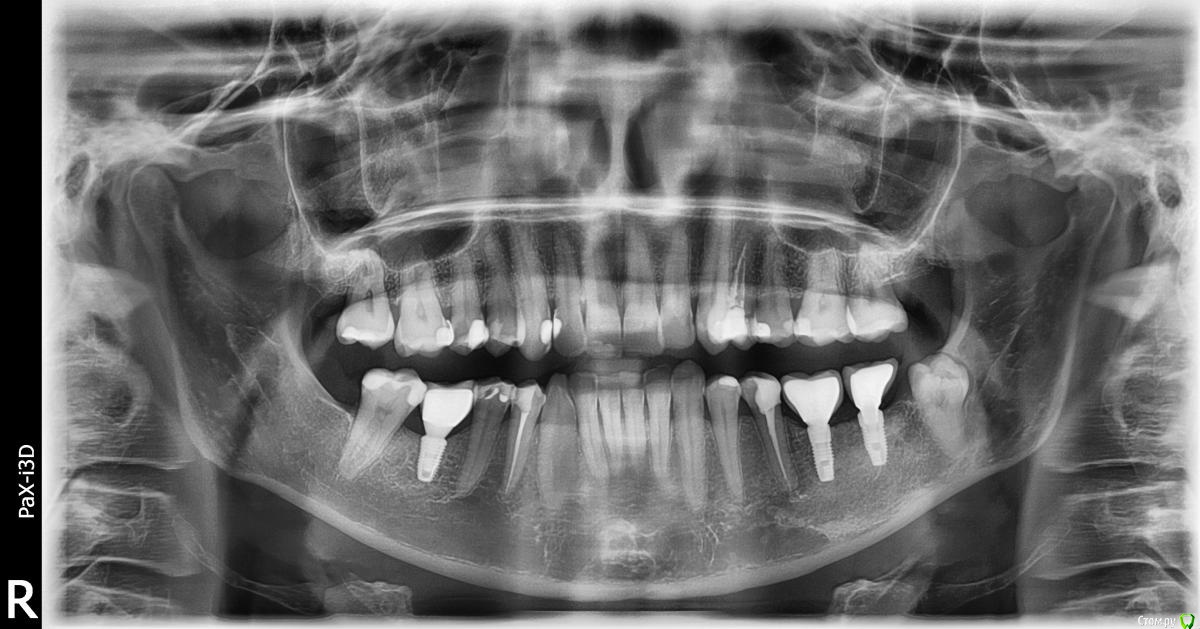

Taste of Honey Опубликовано 22 июня, 2015 Поделиться Опубликовано 22 июня, 2015 Здравствуйте!Будьте добры, помогите с диагнозом:1. Верхняя 4-ка слева - удалили нерв, запломбировали каналы несколько месяцев назад, и все равно есть реакция на горячее. Некоторые врачи говорят (по снимку), что не пройден канал, некоторые - что есть киста... Как Вы считаете?2. Нижняя 5-ка справа - нерв не удален, реагирует на холодное. Кто-то советует не трогать, кто-то - удалять нерв...3. И оба зуба - под коронку. ???Помогите, пожалуйста, разобраться: что же мне все-таки делать с ними?Большое спасибо! Ссылка на комментарий

Чертков Александр Опубликовано 22 июня, 2015 Поделиться Опубликовано 22 июня, 2015 2.4 - перелечивать + коронка4.5 - похоже на кариес или клиновидный дефект (депульпировать нет необходимости) 2 Ссылка на комментарий

Гарриевич Опубликовано 22 июня, 2015 Поделиться Опубликовано 22 июня, 2015 сделайте прицельный снимок верхней четверки, скорее всего перелечивать и покрывать коронкойнижняя 5 удаления нерва скорее всего не требует, нужно искать либо нарушение прилегание пломбы либо кариес или клиновидный дефект 1 Ссылка на комментарий